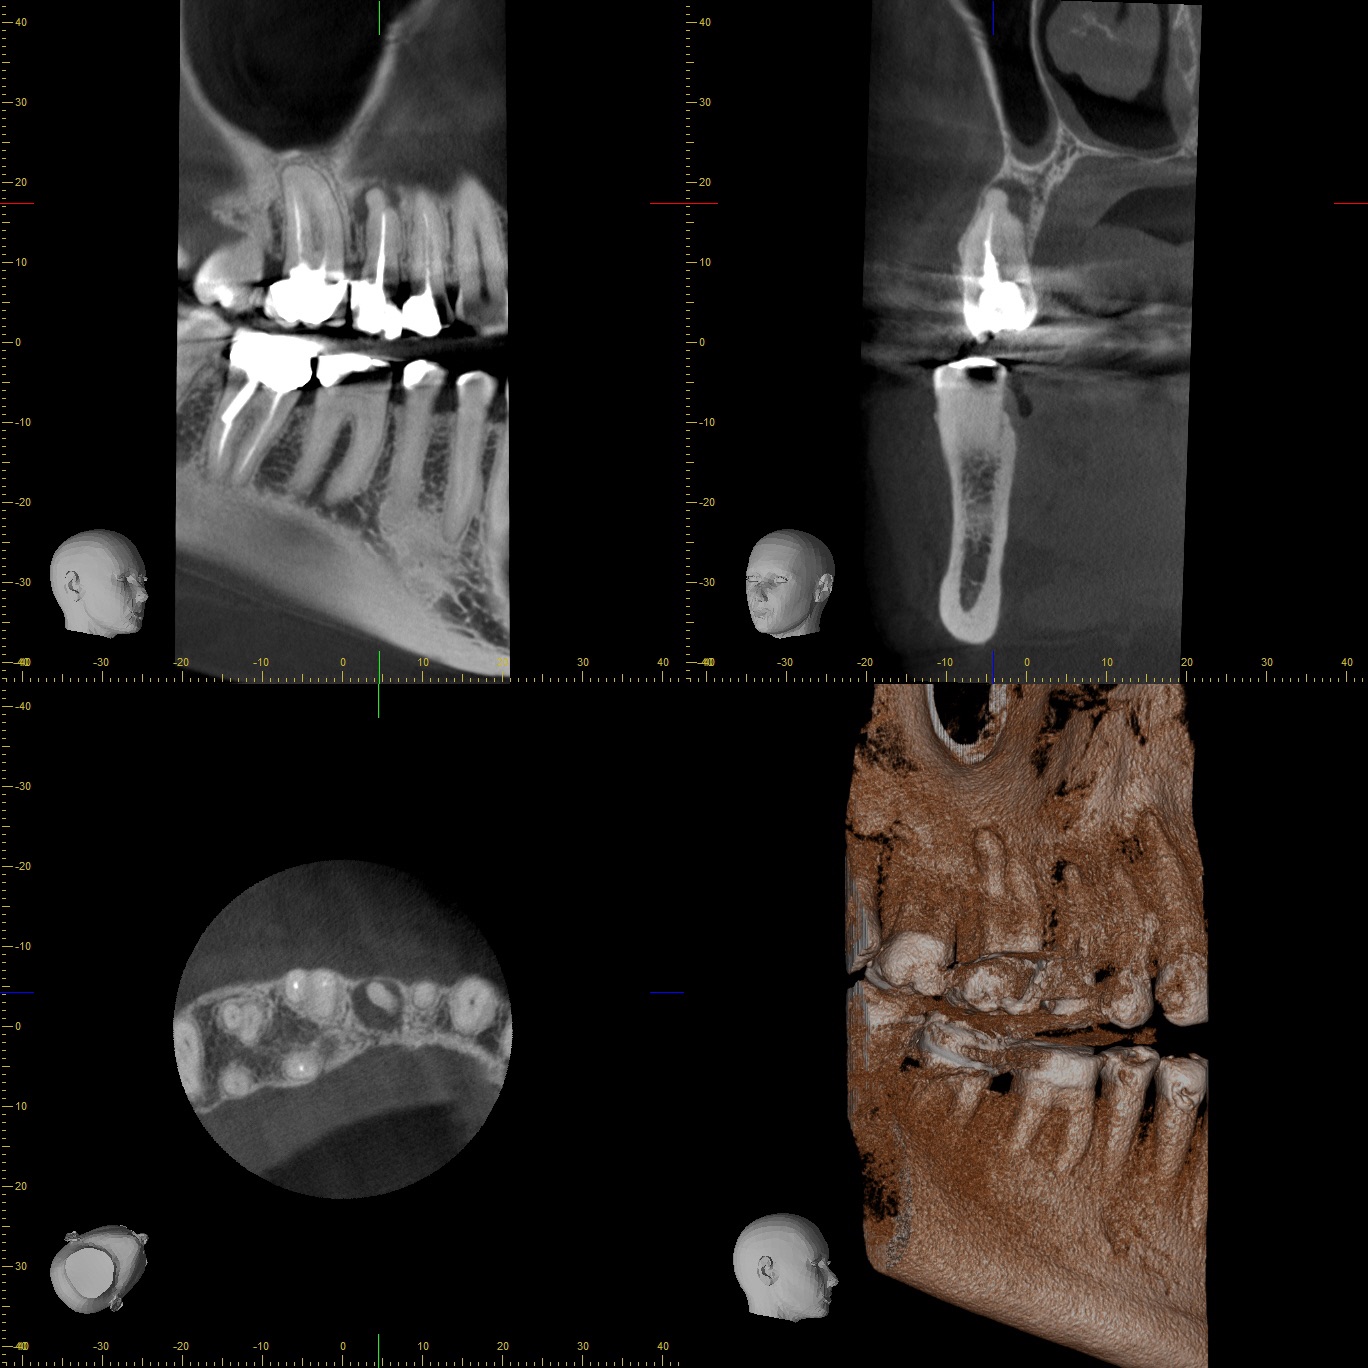

8693 Veröffentlicht 16. Oktober 2019 am 1368 × 1368 in Recall und Verlauf eines endodontischen Falles